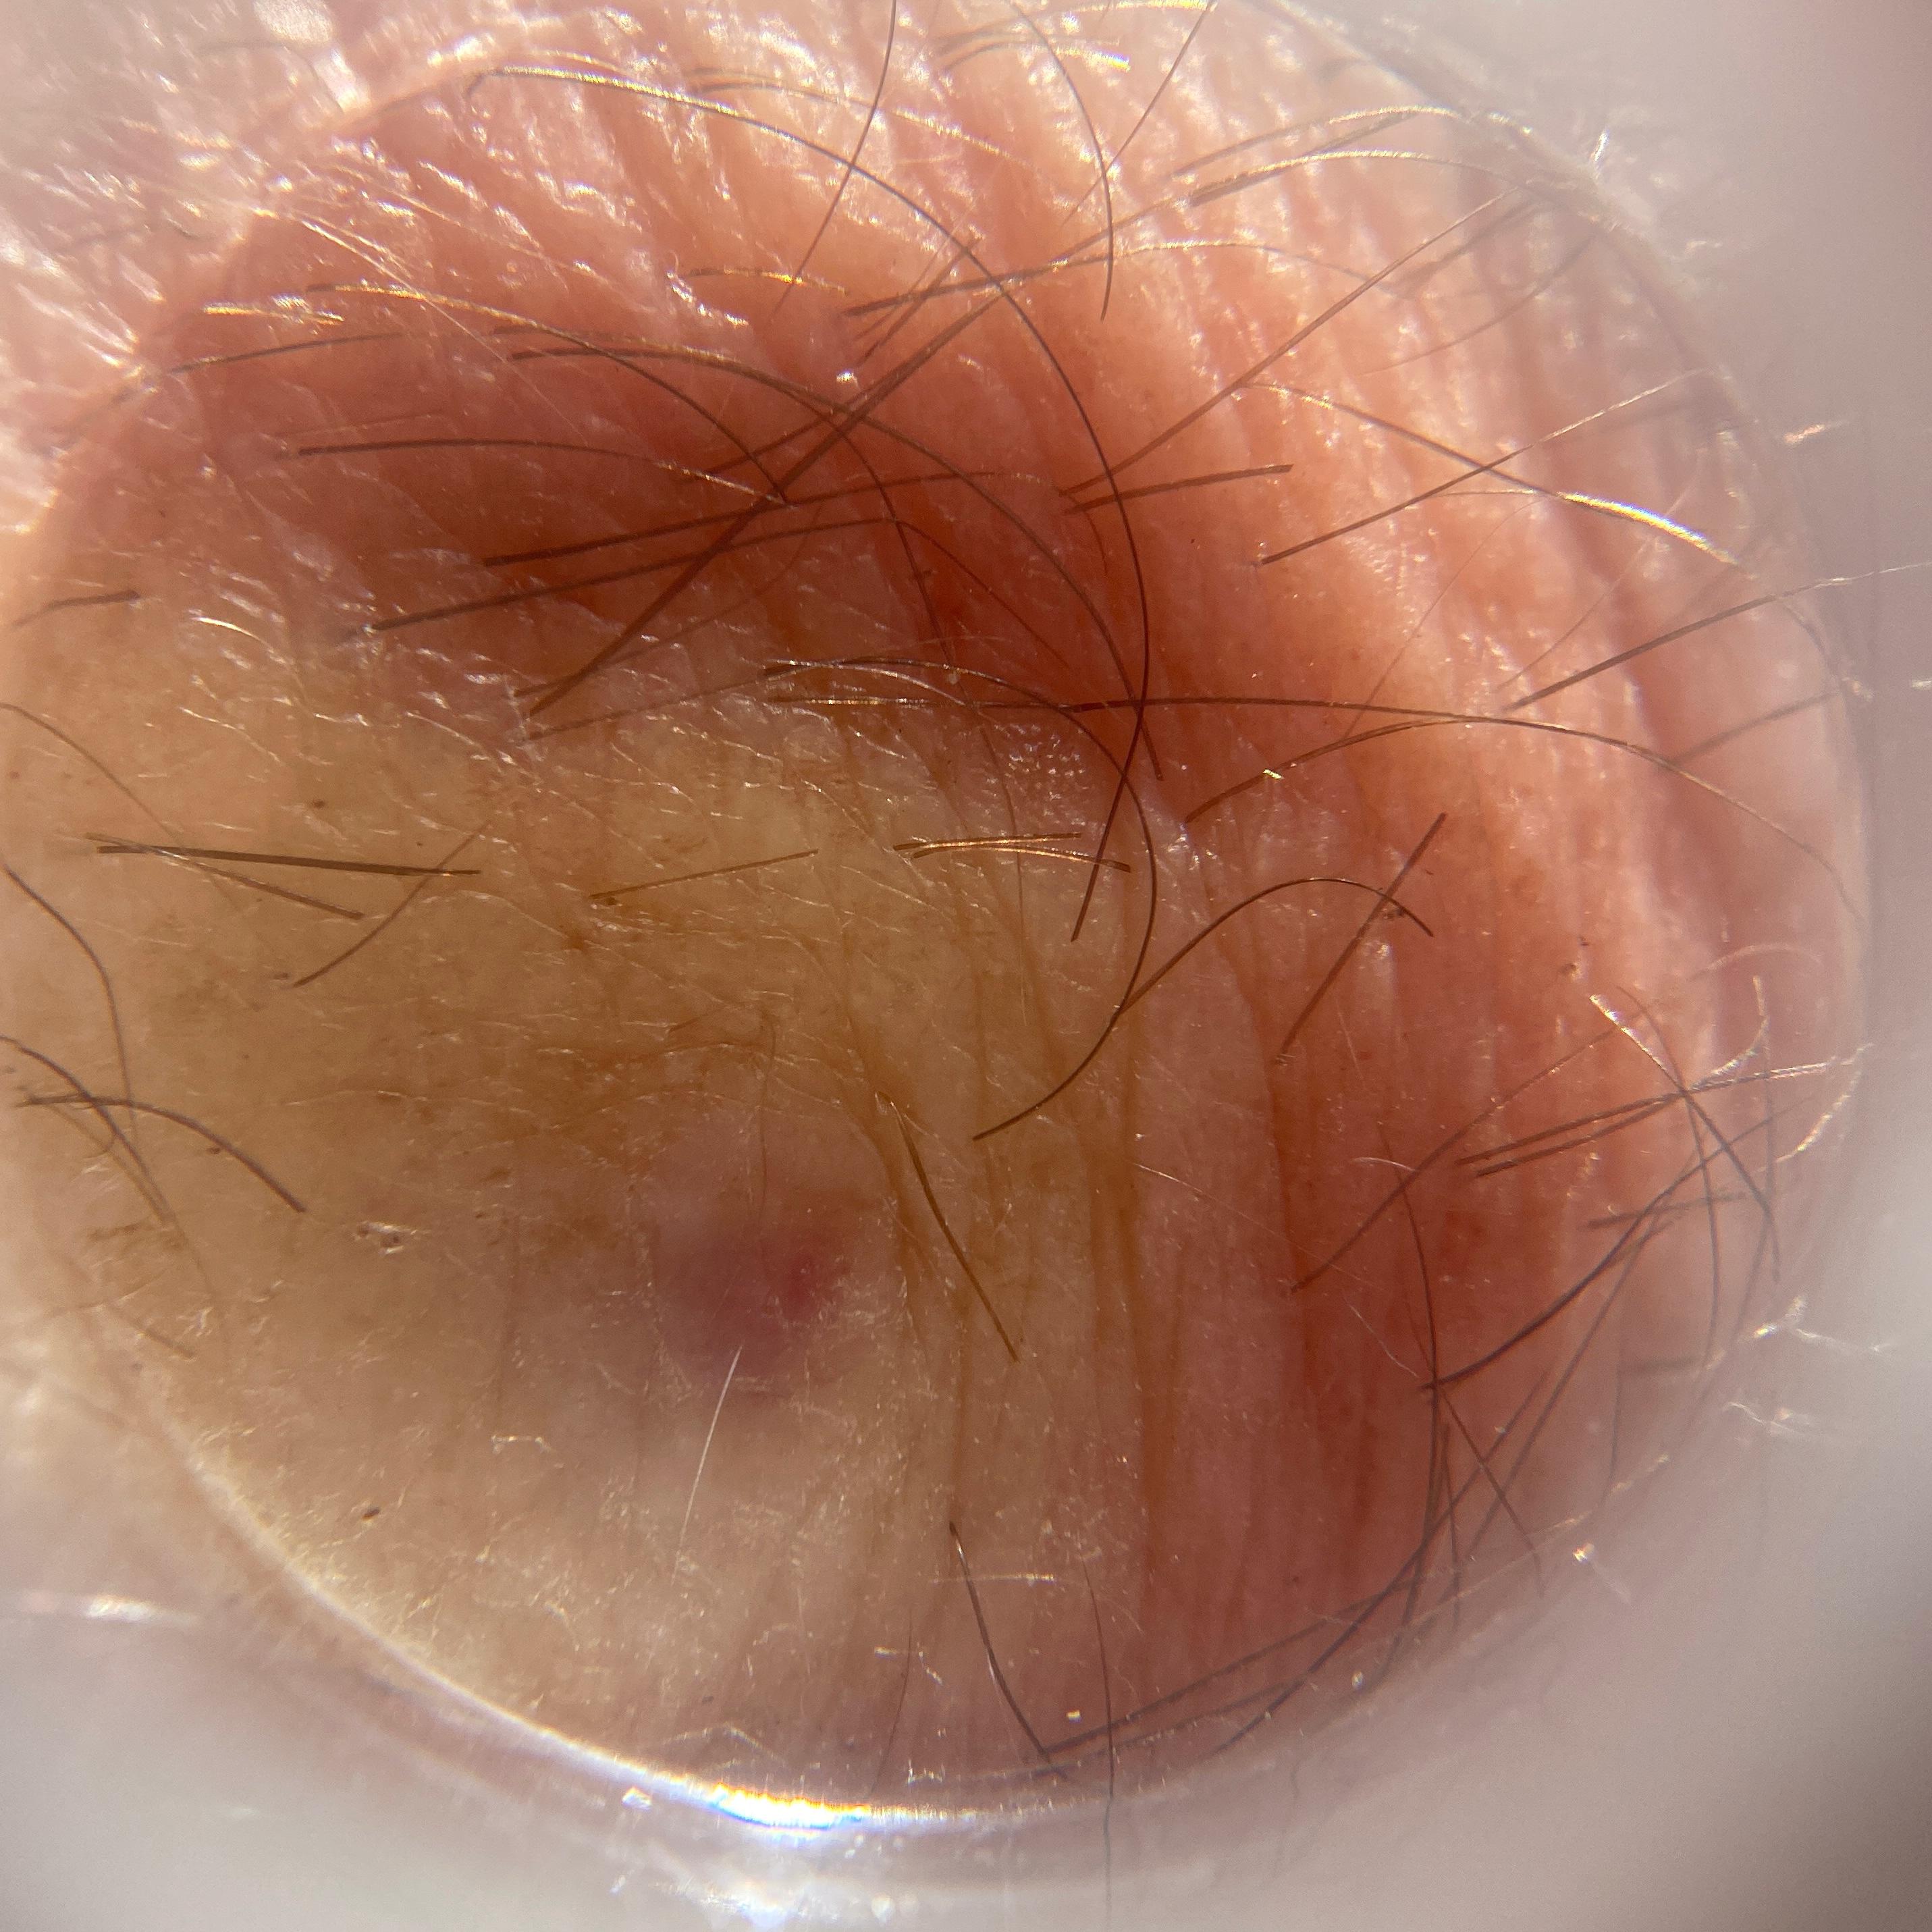

ISIC_7519464

IP_3612490

IL_7662406

Clinical

Field Value

acquisition_day 84

age_approx 70

anatom_site_1 Head and neck

anatom_site_general head/neck

diagnosis_1 Benign

family_hx_mm True

fitzpatrick_skin_type I

image_manipulation instrument only

image_type dermoscopic

lesion_id IL_7662406

patient_id IP_3612490

personal_hx_mm True

sex male